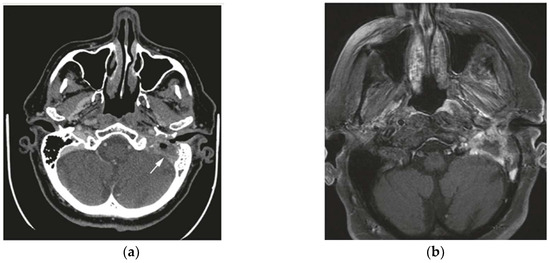

Decoding Temporal Bone Carcinoma: The Role of CT and MRI in Precision Staging

Primary squamous cell carcinoma (SCC) of the temporal bone is an extremely rare malignancy, comprising only 0.2% of head and neck cancers. There is currently no universally accepted staging system for these tumors. This study evaluates the utility of the Pittsburgh staging system [...] Read more.

Primary squamous cell carcinoma (SCC) of the temporal bone is an extremely rare malignancy, comprising only 0.2% of head and neck cancers. There is currently no universally accepted staging system for these tumors. This study evaluates the utility of the Pittsburgh staging system for temporal bone SCC, examines prognostic factors, and reports clinical outcomes. A retrospective review was conducted on a small cohort of 15 patients diagnosed with temporal bone SCC between 2020 and 2023. Imaging included high-resolution CT and MRI (T1W, T2W, and DWI). Staging accuracy was assessed, and Cohen’s Kappa coefficient was used to compare radiological and pathological staging. Results showed a 73% accuracy in preoperative radiological staging, with higher agreement for T3/T4 tumors (86%) compared to T1/T2 (63%). MRI provided additional information, revealing dural enhancement in two patients and parotid involvement in one. Survival analysis indicated 100% survival in T1/T2 patients, 25% in T3, and 0% in T4, supporting the prognostic value of the Pittsburgh system. While limited by the small sample size, the study confirms that the Pittsburgh staging system offers a reliable approach to stratifying patients with temporal bone SCC and underscores the importance of combined CT and MRI for accurate staging and treatment planning. Full article